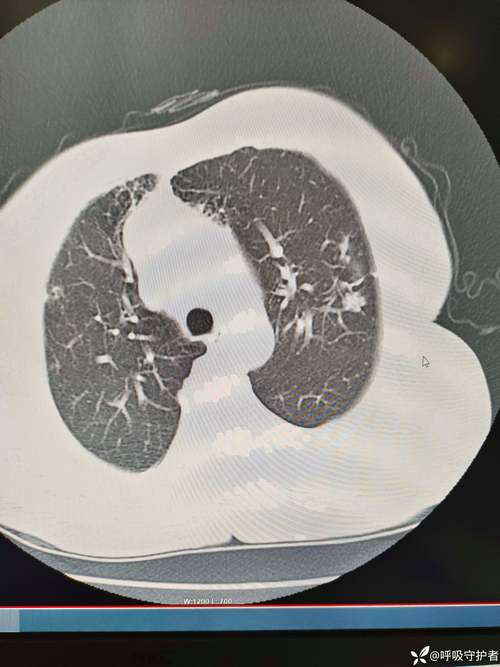

(图片来源网络,侵删)- 开颅手术后患者需要绝对卧床,肺部活动量减少,肺底部的痰液不容易咳出,容易淤积,成为细菌滋生的“温床”。